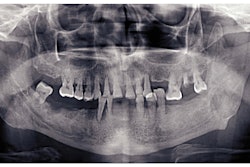

Researchers from Marquette University in Milwaukee will study how aging and periodontal disease affect the connective tissue that absorbs the pressure of chewing.

Funded by a seven-year grant from the National Institutes of Health (NIH), researchers will explore how getting older and gum disease affect cementum, the tissue that attaches the tooth to the gum and absorbs the stress of masticating.

For the first two years of the study, Reis will compare healthy and diseased cementum from human teeth across different age groups. From there, she will create a profile of aging cementum by identifying its biomechanical, structural, and mechanical features. This profile will include demonstrating how aging aggravates periodontal inflammation.